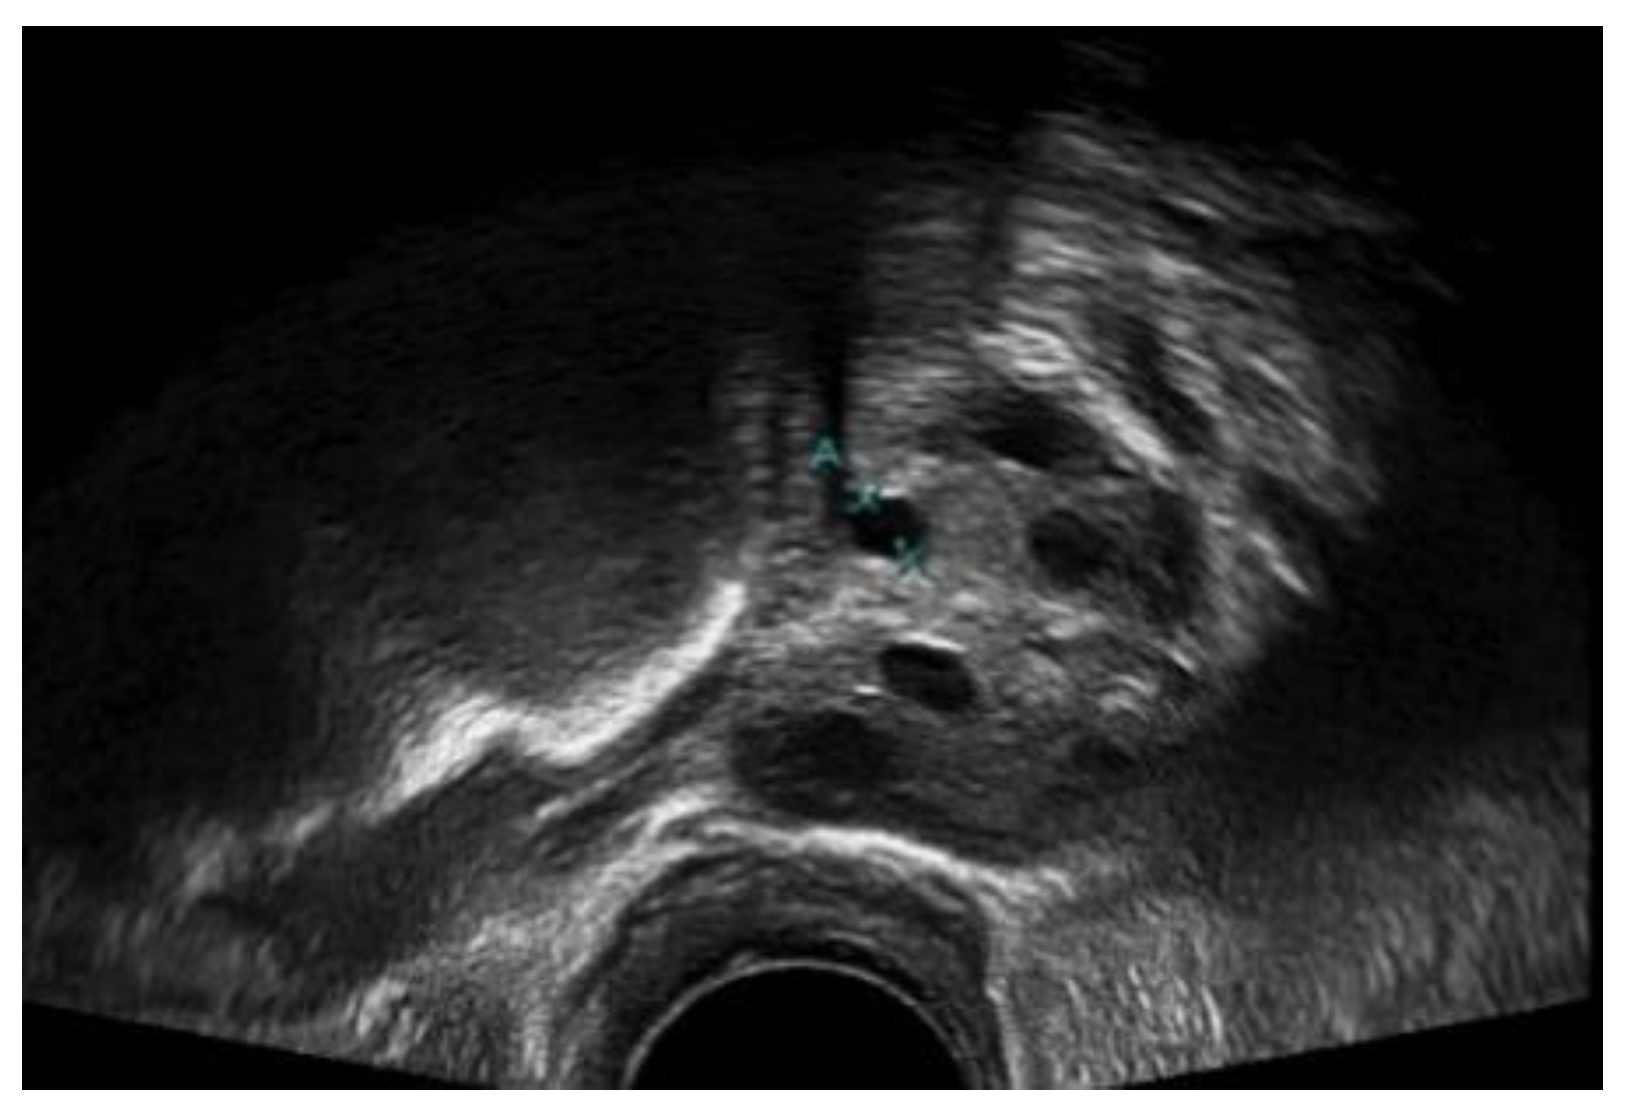

Figure 12 presents a comparison of the classical Chan–Vese and proposed methods with the follicles marked by medical experts. The original ultrasound image is shown in Figure 12a. The image is of poor quality due to speckle noise disturbances, and the boundaries between follicles are poorly visible. In Figure 12b, the red circles are follicles marked by medical experts, showing which of the dark regions are the follicles. Figure 12c shows that the classical Chan–Vese method was able to recognize all small-sized follicles in the ultrasound image. The follicles close to the rear of the ultrasound had a high dark intensity, similar to their boundaries. Otherwise, the follicles detected were relatively small in size due to the inhomogeneity of the ultrasound image. By contrast, the Chan–Vese method is suitable for homogenous images [40]. Figure 12d shows that the follicles were recognized according to the area marked by medical experts. Even though the detected follicles were nearly the same size as the marked ones, some other areas were also detected as follicles. These areas were capillaries in the ovary ultrasound that had similar intensities to the follicles in the ovary.

Figure 12.

Comparison images of different segmentation methods. (a) Original ultrasound image; (b) follicles marked by medical expert; (c) classical Chan–Vese method; and (d) Otsu thresholding and the Chan–Vese method.

A comparison of the ground truth and segmented images is shown in Figure 12 and Figure 13. The images obtained using classical Chan–Vese method and the proposed method in Figure 12c,d and Figure 13c,d show that some false follicles were detected, because the pixel intensities in the particular area mimicked the intensities of PCOS follicles. The quantitative values of image segmentation were calculated in order to compare the effectiveness of the methods.